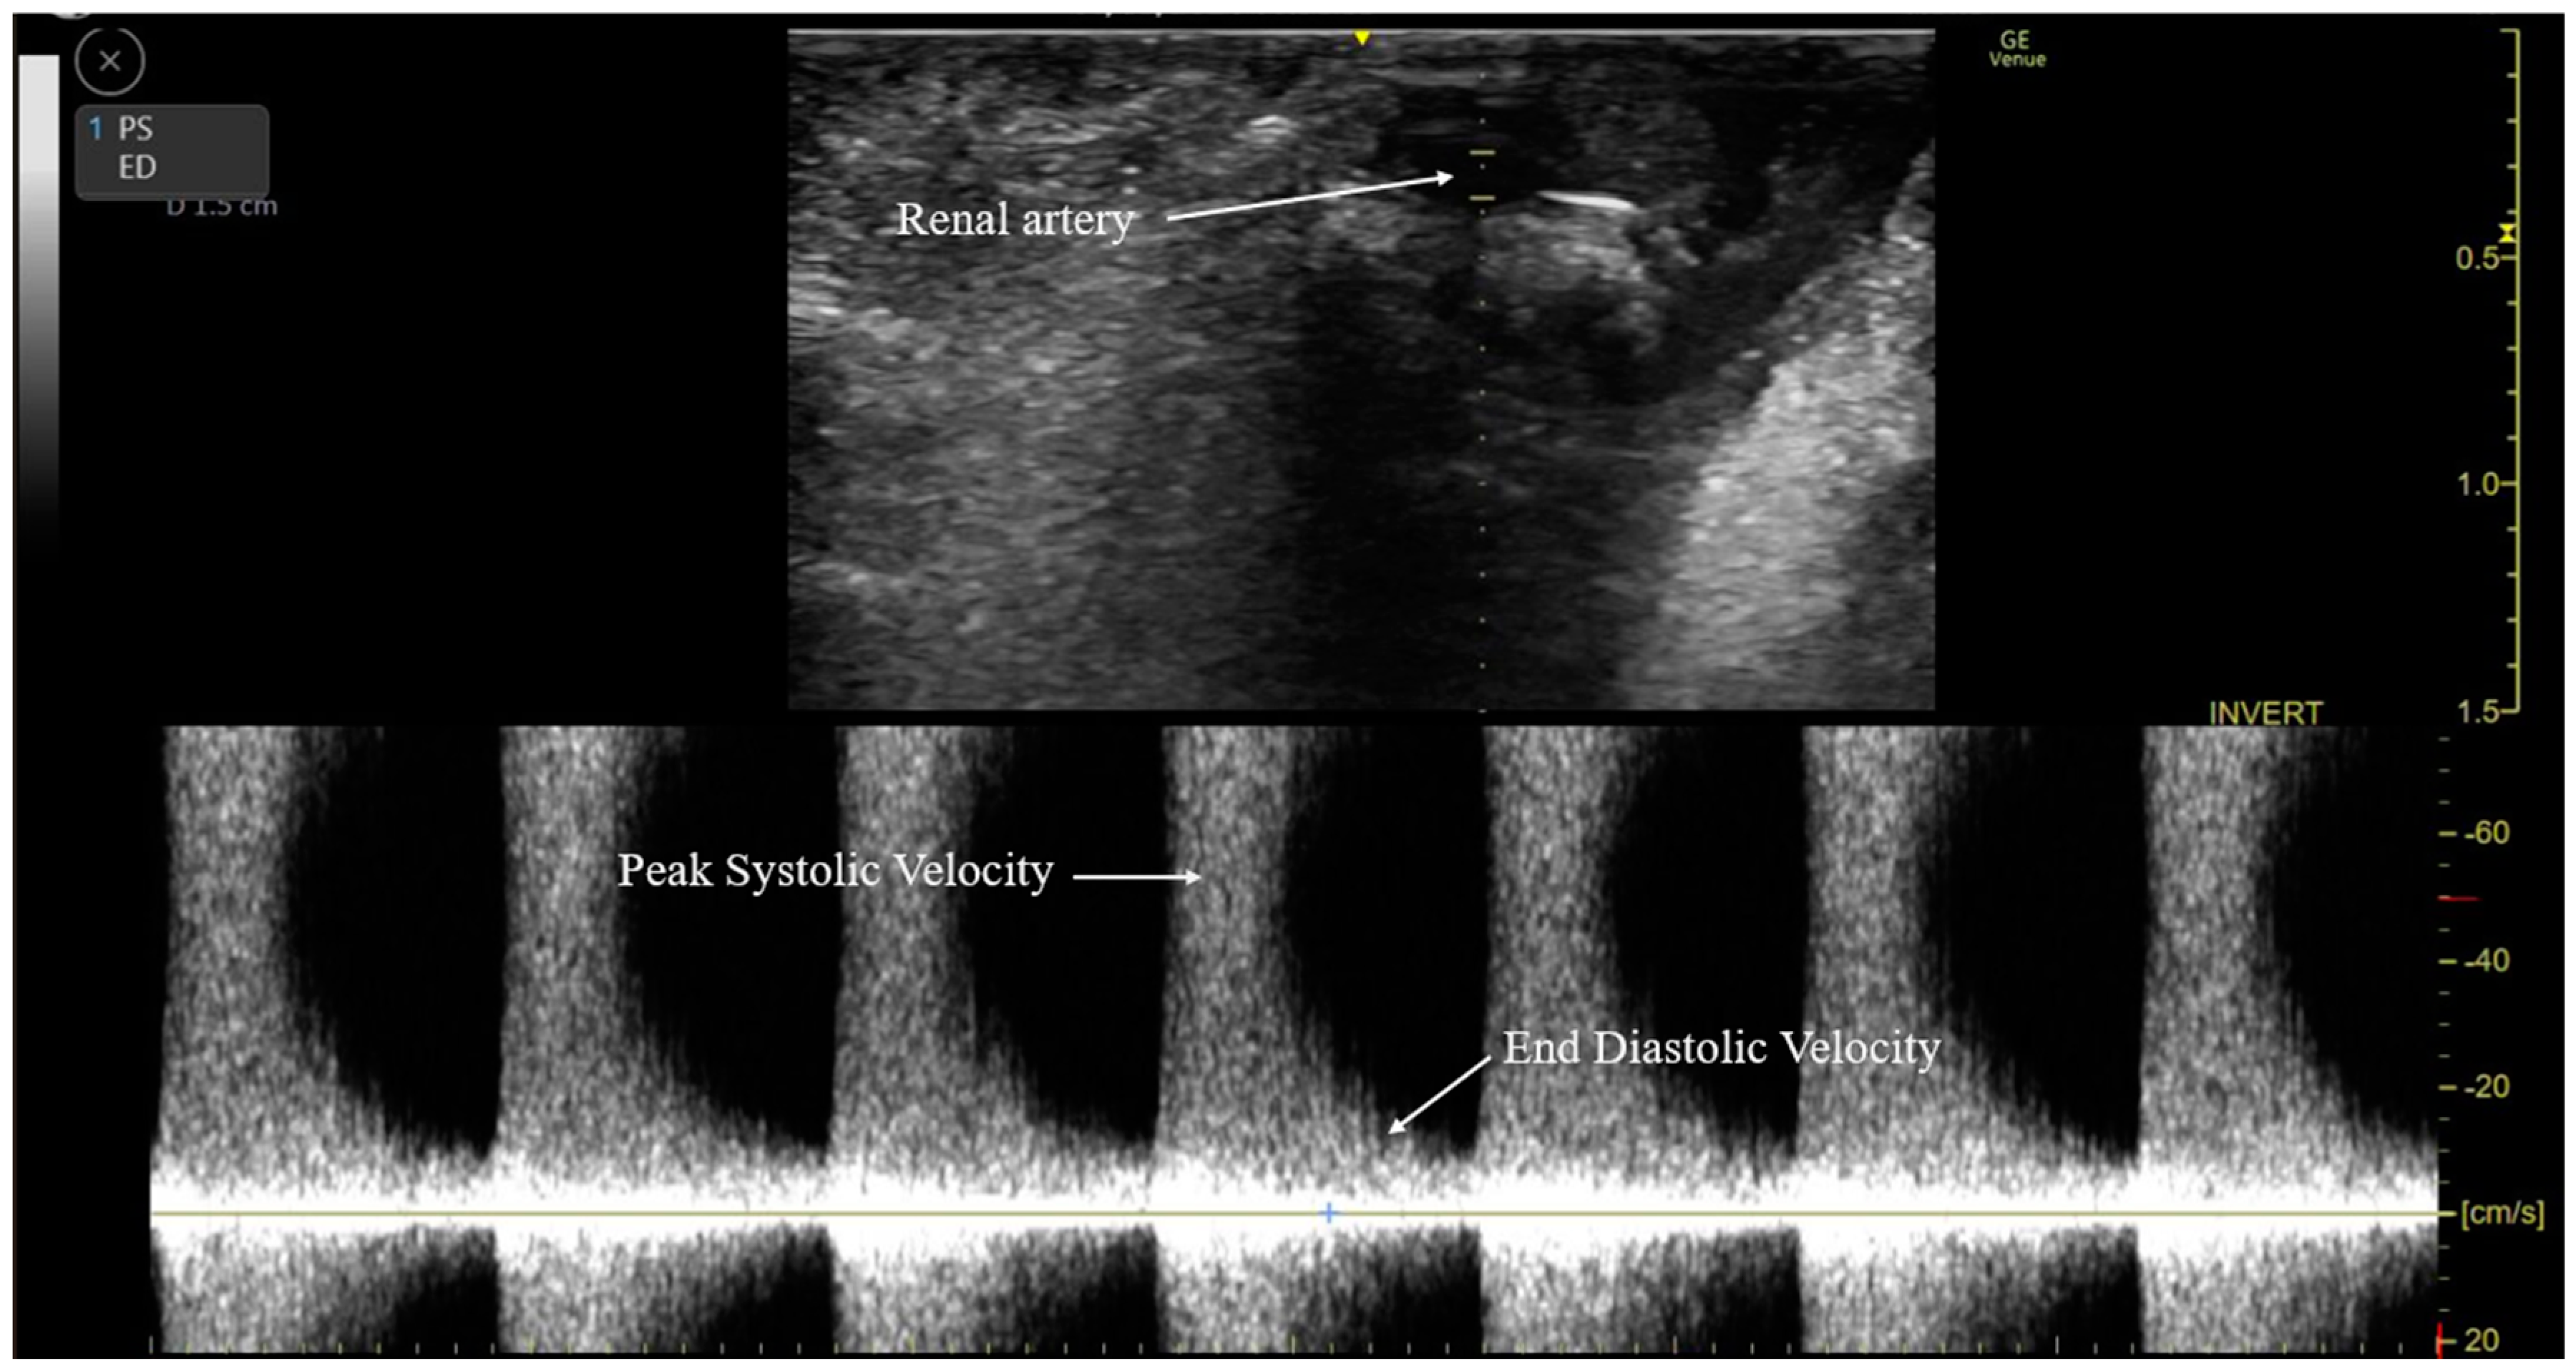

2.5. Intraoperative RARI Measurement